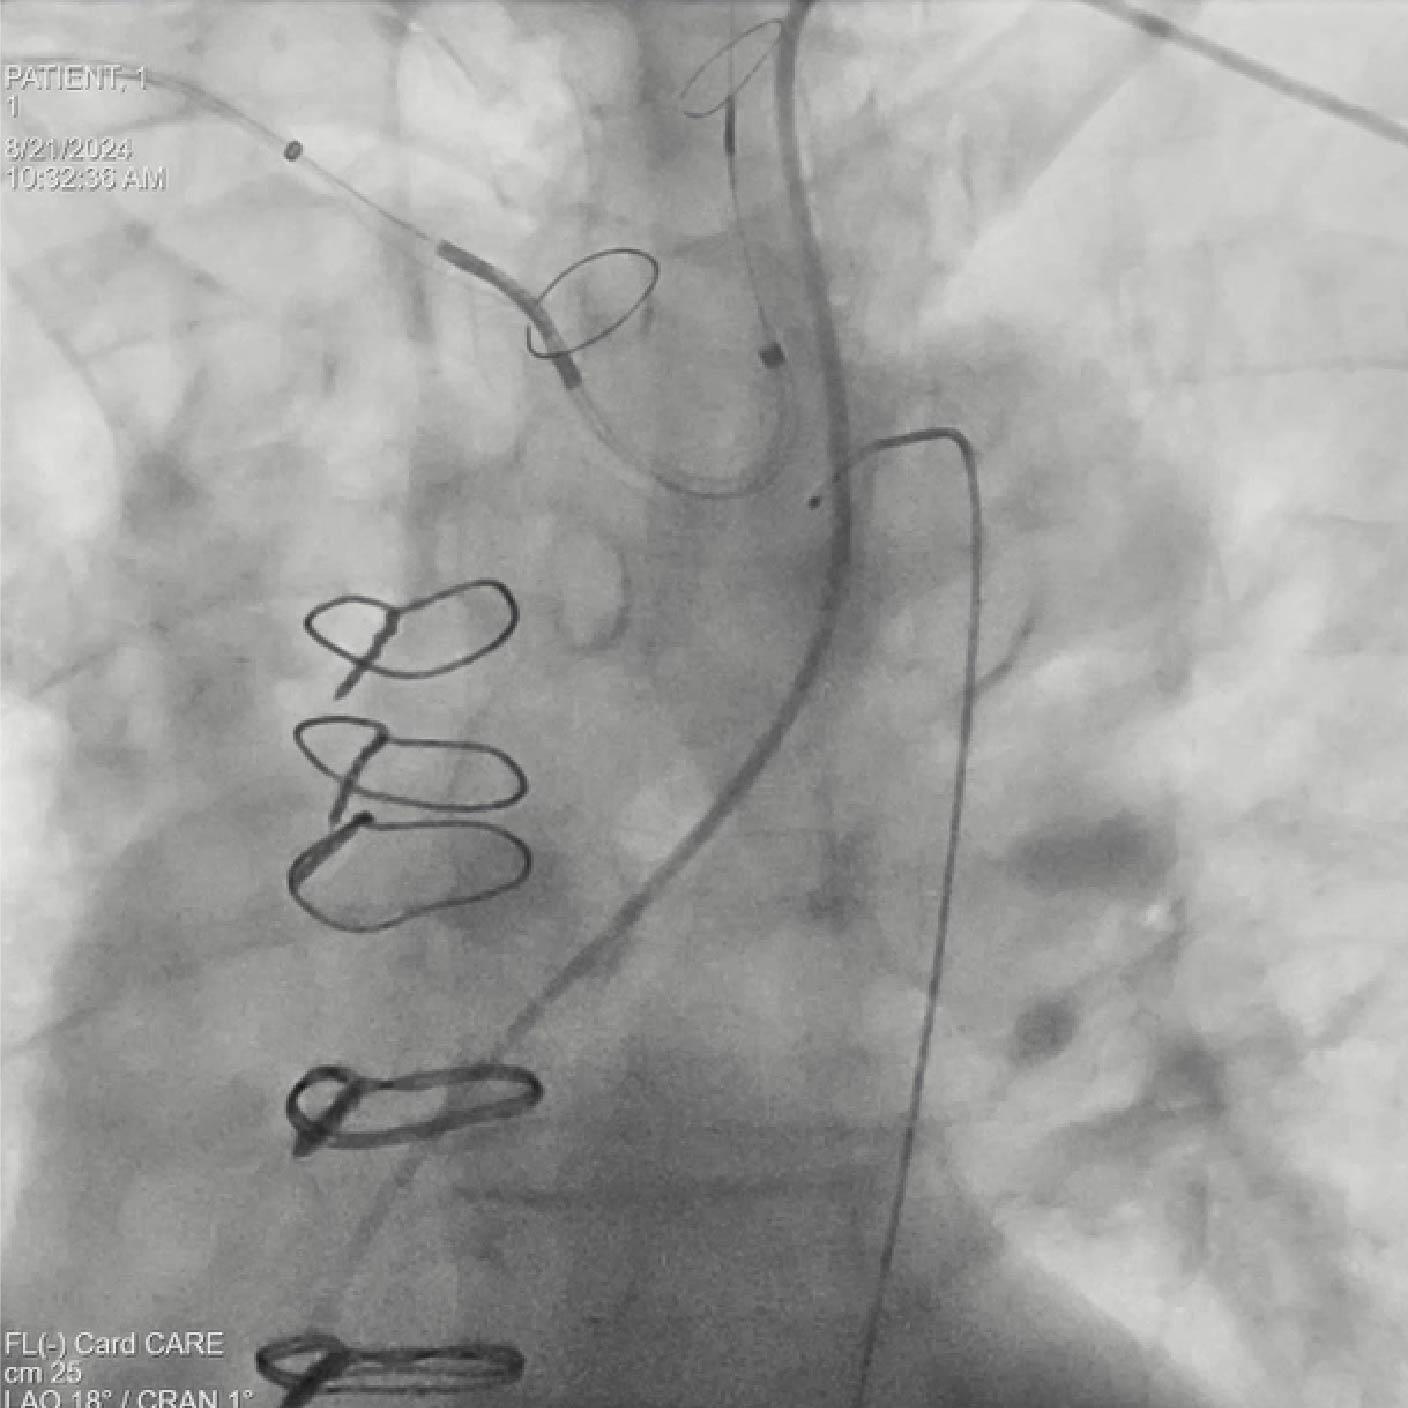

- Despliegue del dispositivo SAPIEN 3

Posicionamiento y despliegue del dispositivo